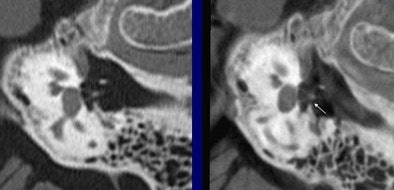

Both modalities produced diagnostic images, but fpVCT produced a significantly higher average sum score (60.8) compared to MDCT (41.5) (p < 0.02). In particular, structures such as the stapedial muscle and the bony walls of the facial nerve canal were much more clearly displayed in fpVCT, Bartling said.

| The flat-panel VCT images of the skull base at right were rated significantly higher in image quality compared to 16-slice MDCT images of the same regions at left, by two readers rating 21 features independently. Images (from top to bottom) include stapes and ovale window niche (above), facial nerve canal (below), maxillofacial region, and implanted microscrews (bottom). All images courtesy of Dr. Sönke Bartling. |